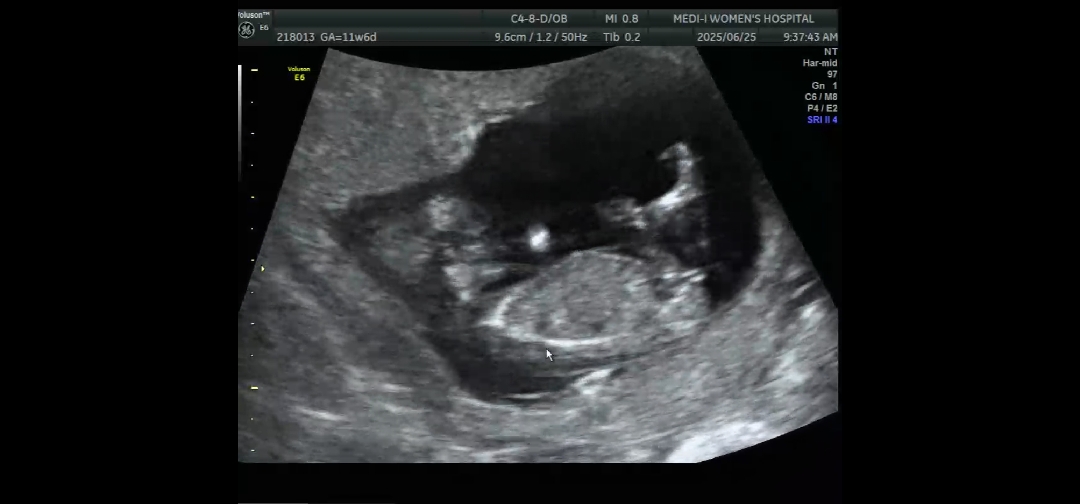

12주차 정밀초음파 각도법 봐주실분ㅠ

생식결절이 맞는걸까요?? 아들인지 딸인지 너무 궁금하네요ㅠㅠ